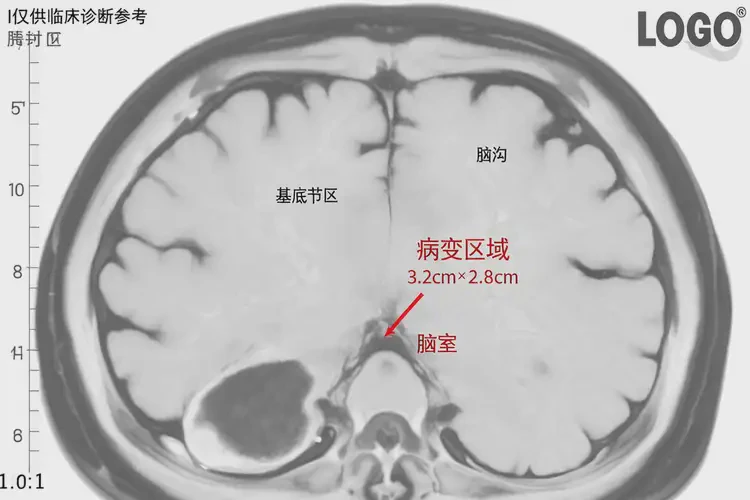

3. 影像學(xué)檢查:如腦部CT或MRI,用于排除其他器質(zhì)性疾病,費(fèi)用一般在500-800元之間。